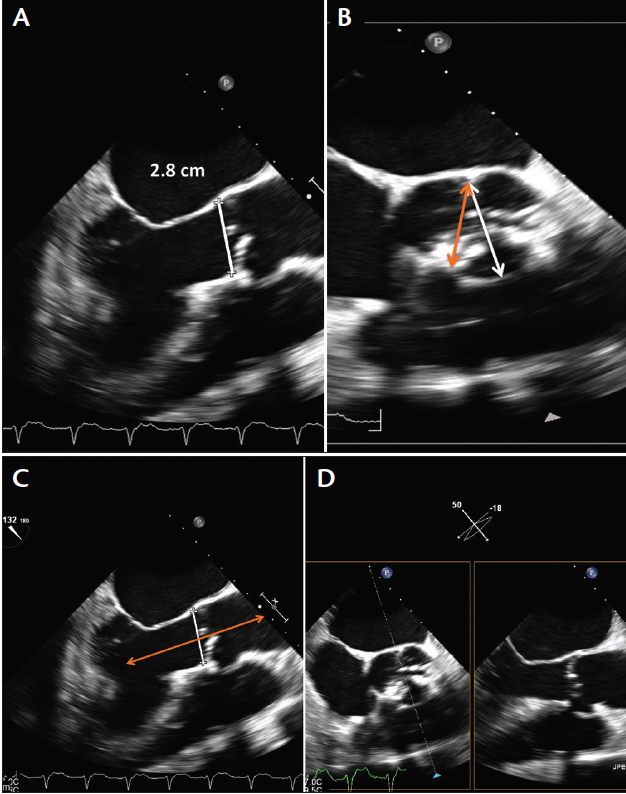

Two-dimensional echocardiography plays a crucial role in transcatheter valve implantation procedures and can also be used in aortic annular sizing. In fact, MDCT and echocardiography may be complementary techniques in this situation. According to the American Society of Echocardiography, the aortic annulus is measured in the parasternal long axis view on transthoracic echocardiography (TTE) or the midesophageal long-axis view on transesophageal echocardiography (TEE).12 The distance is measured between the leaflet insertions of the leaflet on the top of the image to that of the bottom of the image (Figure 1A).

Figure 1. Two-dimensional TEE measurement of the aortic annulus (A). The measurement is made under the aortic valve from the hinge point of one leaflet to another. This measurement should be undertaken in the midesophageal long-axis view of TEE. The orange arrow (B) demonstrates measuring a smaller dimension than what the annulus actually is. This is one of the limitations of 2D TEE annular dimension measurement. The white arrow (B) demonstrates the true sagittal measurement. However, because the annulus is not a perfect circle, the coronal measurement may be larger, again underestimating the annular size. Note that the 2D linear measurement is perpendicular to the long axis of the aorta (C). Biplane imaging across the short axis of the aortic valve may help prevent some of the issues with off-axis measurements of the aortic annulus (D).

The problem with this technique is that measurements made using the leaflet insertions may not transect the full diameter of the aortic annulus; instead, the measurement could be a tangent across the aortic annulus, thus grossly underestimating the annulus size (Figure 1B). When measuring the aortic annulus, care should be taken to exclude or to measure around the significant calcification that can be frequently present along leaflet attachments in patients with severe aortic stenosis. In addition, one must ensure that the measurement of the annular plane is perpendicular to the long axis of the aorta, as this can prevent some of the problems encountered with tangential measurements of the annulus (Figure 1C).

In biplane imaging, bisecting the short axis of the aortic valve produces a longitudinal image and may help in obtaining the largest annular diameter (Figure 1D). This may overcome some of the issues of tangential measurements of the annulus. Despite the limitation of 2D echocardiography for annular sizing, it can give a quick idea of what the appropriate valve size would be for any given patient. For instance, in the case of balloon-expandable valves, a 2D linear measurement of 24 mm would imply the use of a 26-mm valve, and a 2D linear measurement of 27 mm would imply the use of a 29-mm valve.